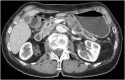

Pancreatic Metastases of Rectal Cancer-Case Report and Literature Review